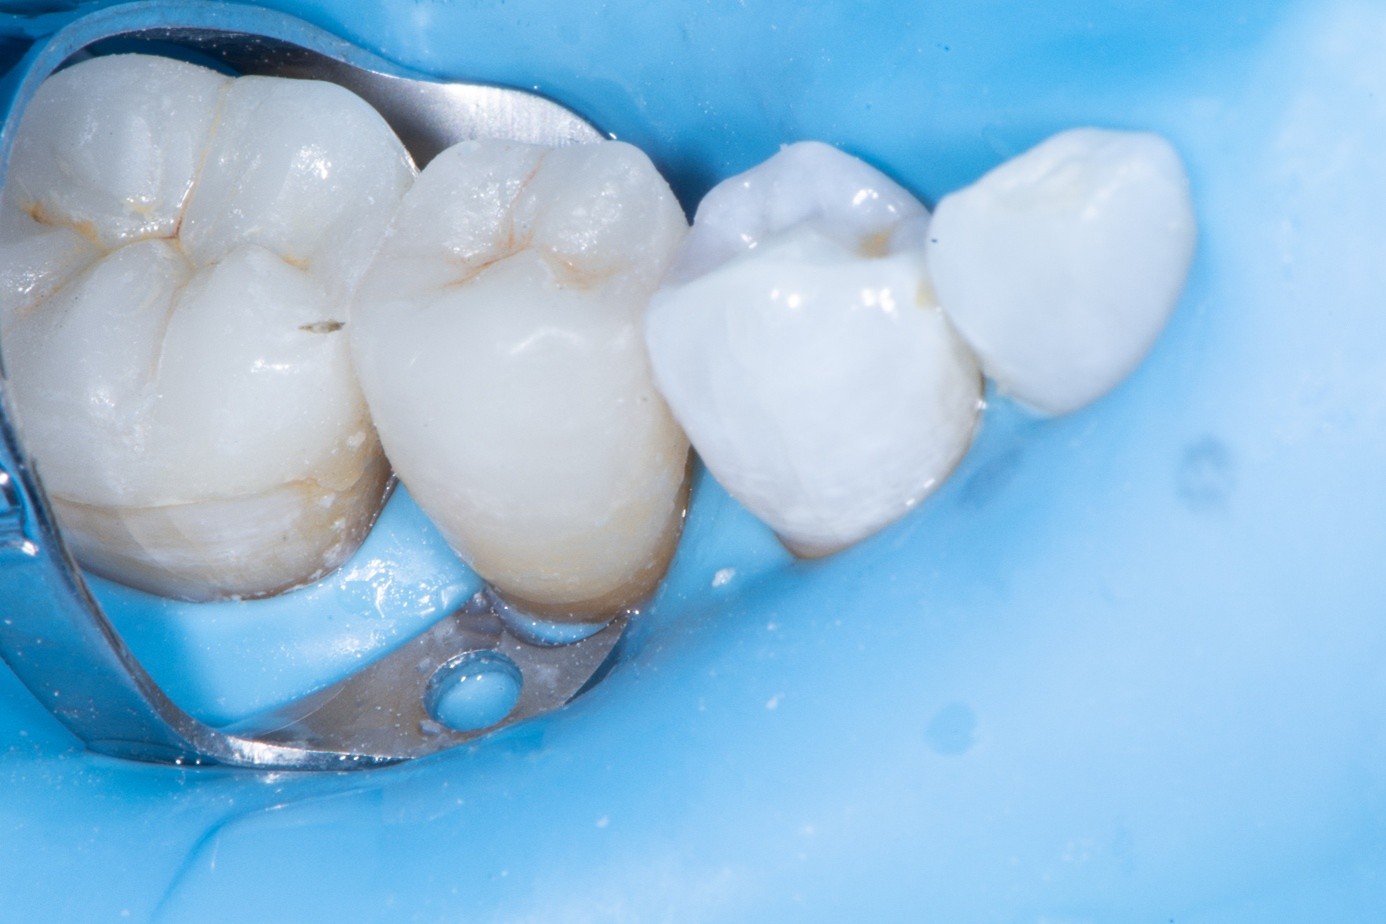

After shade selection and clinical photos, absolute isolation with a rubber dam was achieved. The intaglio surface of the fractured piece was air abraded with glass beads at 2 bars of pressure to remove residual cement. Aluminum oxide powder should be avoided on glass ceramics, as it tends to create microcracks and has shown to decrease bonding strength (Figure 4 and Figure 5).4 The fractured piece was etched with 9% hydrofluoric acid for 120 seconds followed by thorough rinsing for 20 seconds, then scrubbed with 37% phosphoric acid for 60 seconds and placed in an ultrasonic bath for four minutes in distilled water, rinsed, dried, and treated with silane to promote chemical bonding and heat treated at 100 °C for 5 seconds (Figure 6).5,6 The combination of the phosphoric acid scrub and the ultrasonic bath after HF etching helps to remove any calcium salt residues created during HF etching.

(3.) Fractured ceramic piece of the upper lateral incisor showing adhesive and cement remnants on the inner surface. (4. and 5.) At 100X magnification, the glass beads

Figure 3